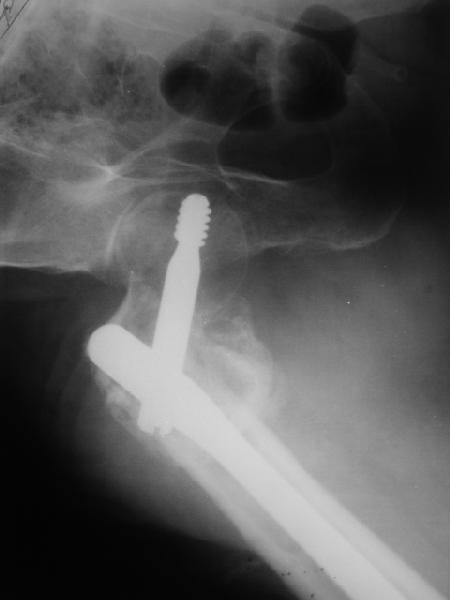

В приложении пример пациента, близкого по картине к тому, что

представил Виктор (варус и смещение периферического отломка на

поперечник кзади). Сделали как раз то, что Виктор исходно намеревался

- аппаратная коррекция и затем гамма.